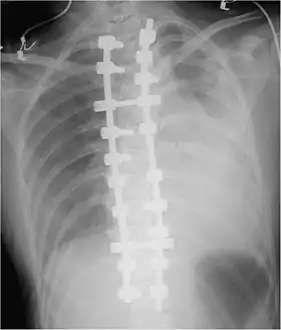

Chest X-ray

Development of hemothorax following lung lesion biopsy

Showing a massive left-sided hemothorax

Right showing a massive right hemothorax

A chest X-ray is the most common technique used to diagnosis a hemothorax.[23] X-rays should ideally be taken in an upright position (an erect chest X-ray), but may be performed with the person lying on their back (supine) if an erect chest X-ray is not feasible. On an erect chest X-ray, a hemothorax is suggested by blunting of the costophrenic angle or partial or complete opacification of the affected half of the thorax. On a supine film the blood tends to layer in the pleural space, but can be appreciated as a haziness of one half of the thorax relative to the other.[5] A small hemothorax may be missed on a chest X-ray as several hundred milliliters of blood can be hidden by the diaphragm and abdominal viscera on an erect film. Supine X-rays are even less sensitive and as much as one liter of blood can be missed on a supine film.[24]